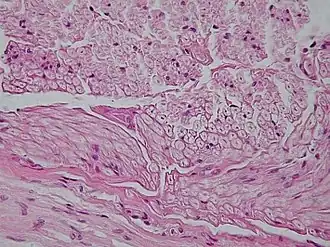

micrografía de tejido conjuntivo un tipo de tejido animal, obtenida con microscopio óptico. | ||